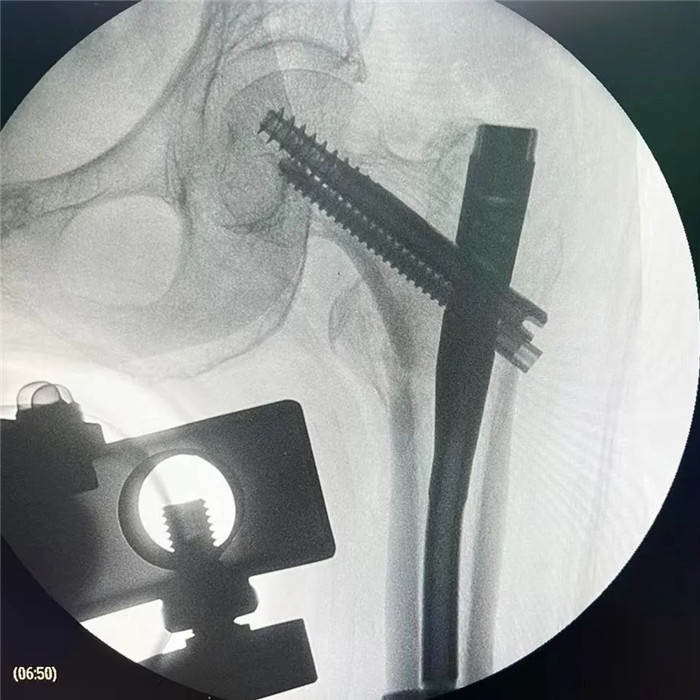

在手術(shù)團隊及患者家屬的大力支持下,羅軍主任團隊為洪阿婆實施了閉合復(fù)位INTERTAN內(nèi)固定術(shù)。雖然手術(shù)風險較大,但憑借精湛的技術(shù)及豐富的臨床經(jīng)驗,手術(shù)十分成功而且僅僅用了1個小時,術(shù)中出血不多,術(shù)后患者恢復(fù)得很好,第二天就可以在起床活動,極大的提高了患者的生活質(zhì)量,避免了長期臥床造成的并發(fā)癥。

目前我院骨科對于高齡老年人股骨頸骨折行人工髖關(guān)節(jié)置換手術(shù)技術(shù)已經(jīng)非常成熟,術(shù)后2~3天就可以下地活動,可以明顯提高高齡老人的生活質(zhì)量,效果良好。